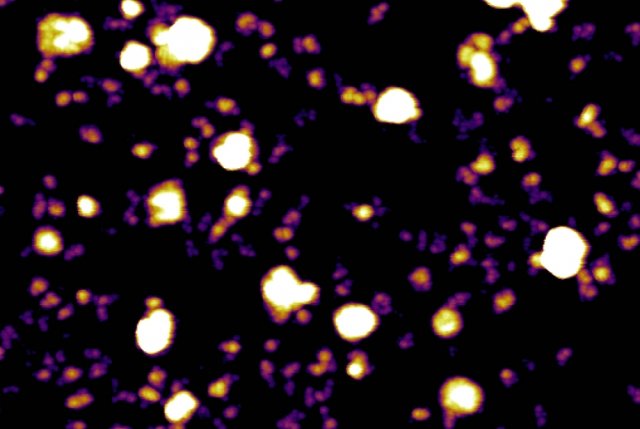

Hình 1: Hình ảnh Exosomes (cấu trúc giống quả bóng trắng) và Exomeres (tím và vàng) được chụp

bởi kính hiển vi lực nguyên tử AFM (Atomic Force Microscope)

Exomere là hạt quan trọng nhất được tiết ra bởi các tế bào ung thư. Chúng nhỏ hơn , có cấu trúc và chức năng khác biệt với exosome. Exomere chủ yếu kết hợp với các tế bào trong tủy xương và gan, nơi chúng có thể làm thay đổi chức năng miễn dịch và sự trao đổi chất của thuốc. Exomere có đường kính nhỏ hơn 50 nanomét, so với các exosome nhỏ (Exo-S) có đường kính từ 60 đến 80 nanomet và các exosome lớn (Exo-L) có đường kính từ 90 đến 120 nanomet. Exosome và exomere cũng có các đặc tính sinh lý khác nhau, chẳng hạn như độ cứng và điện tích có thể ảnh hưởng đến vận chuyển của chúng trong cơ thể. Exosome và exomere cũng khác nhau trong cách ảnh hưởng đến ung thư. Exomere mang enzyme trao đổi chất vào gan, cơ quan này là trung tâm của việc chuyển hóa các thuốc thành các dạng không độc hại. Phát hiện này gợi ý rằng các tế bào ngoại lai tập trung vào gan để “tái lập trình” chức năng trao đổi chất của nó để thúc đẩy phát triển của khối u. Ngoài ra, exosome và exomere cũng có thể phát hiện được trong dịch sinh học của cơ thể như dịch bạch huyết có thể cho phép phát triển các chất chỉ điểm sinh học để phát hiện sớm ung thư hoặc các bệnh lý khác. Điều này sẽ giúp chúng ta hiểu rõ hơn về sinh bệnh học của ung thư, hướng dẫn các quyết định điều trị và phát triển các liệu pháp mới.